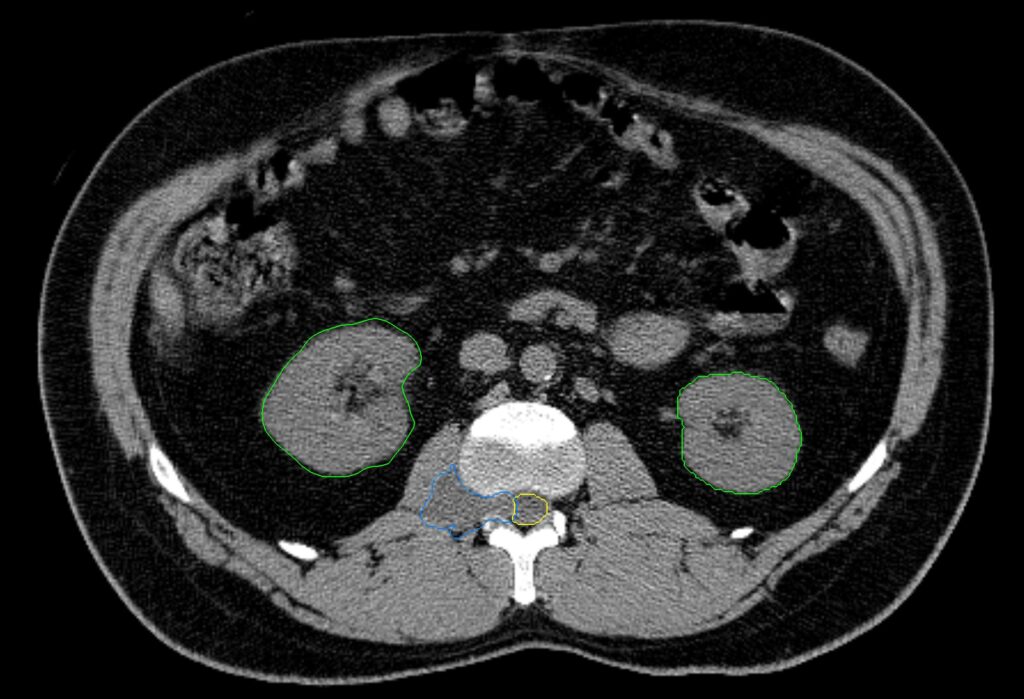

Planning CT Images

New Conformality Index (nCI)

nCi = 1.47

Gradient Index (GI)

GI = 4.24